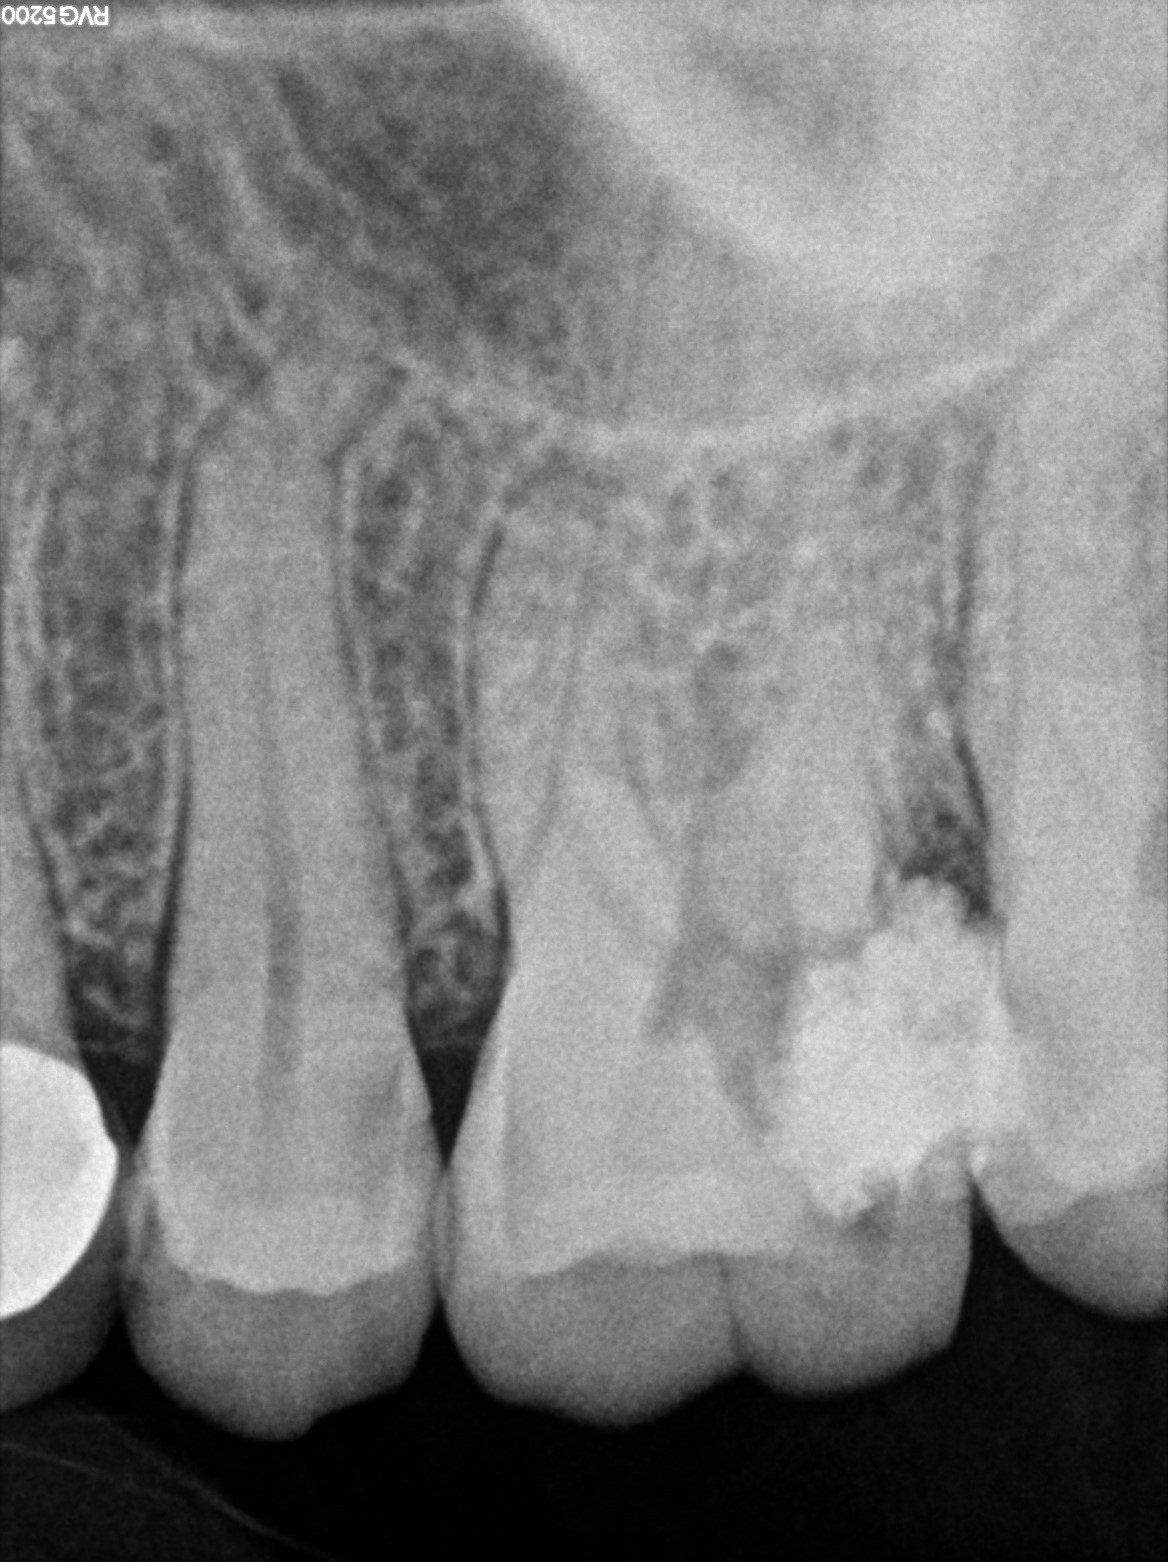

Dental Radiographs FHIR: DocumentReference · LOINC 24641-7

R56 (2).jpg

24641-7